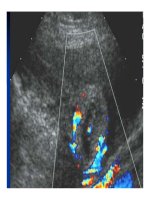

2. siêu âm:

I. Các kỹ thuật thăm khám hình ảnh

- Dịch trong khoang phúc mạc: Túi cùng Douglas, rãnh

thành-đại tràng, khoang Morisson, khoang lách-thận.v.v.

- Tìm tổn th- ơng vỡ tạng đặc do chấn th- ơng.

- Có thể tìm vị trí trí và nguyên nhân của tắc ruột.

- Ngoài ra, siêu âm cũng có thể xác định đ- ợc khí trong ổ

bụng ở các tr- ờng hợp thủng tạng rỗng.